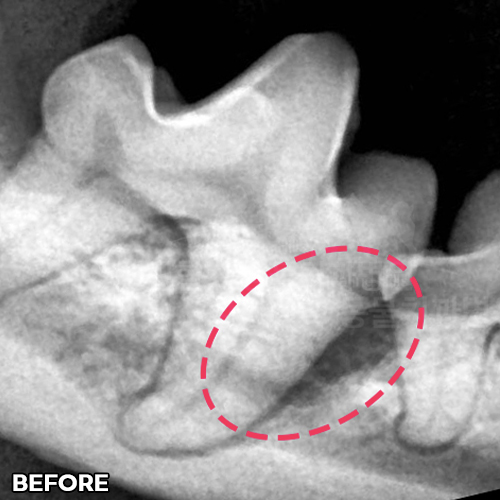

턱뼈 부러뜨리는 강아지치근단농양! 2.3kg 초소형견 발치하지 않고 신경치료하여 자기치아 살리는 힐링힐스